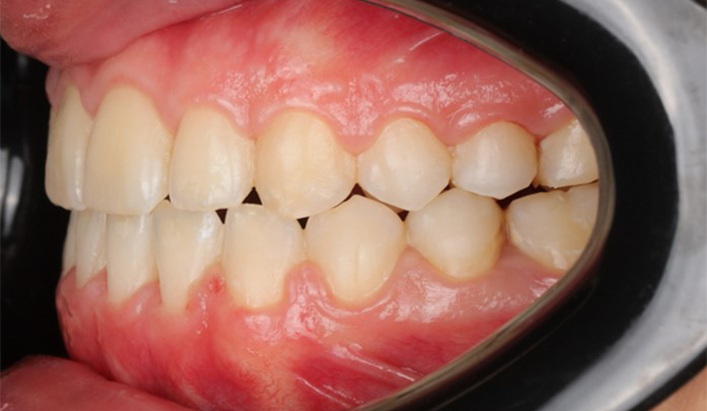

A 22-year-old female patient presented with a Class III malocclusion. She does not like her own profile. Her facial profile was straight with a slightly retrusive maxilla, the upper incisors were within normal inclination, and the lower incisors were retroclined. Bolton discrepency is on mandible for 6 teeth. A retruded upper lip and a normally positioned lower lip were noted. There was also a marked lack of midface support, and the constricted dental arches resulted in a narrow smile and pronounced dark buccal corridors.